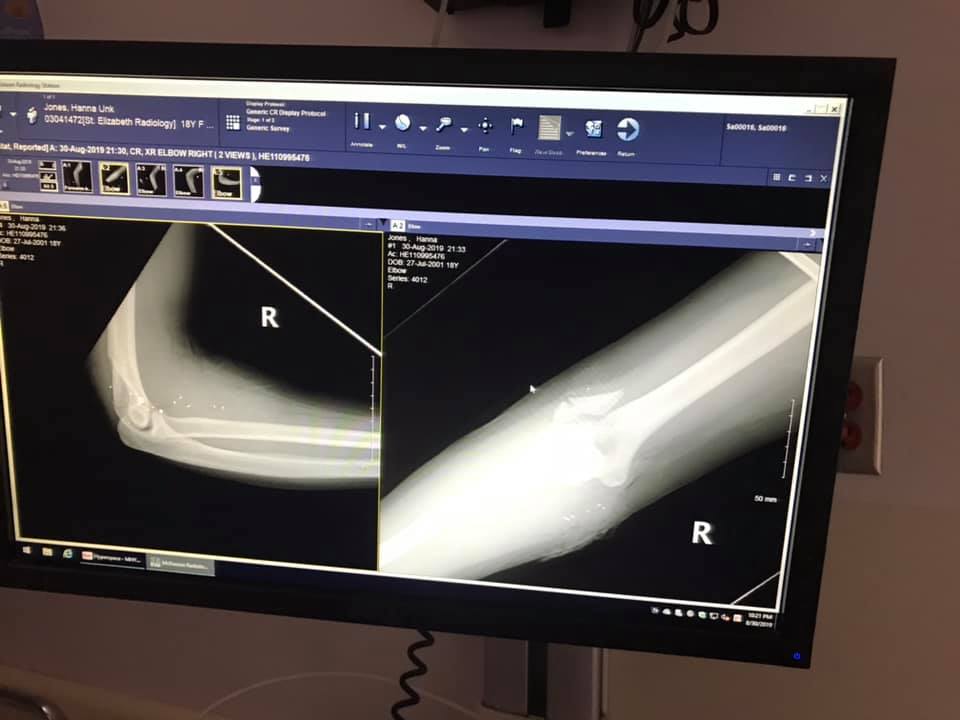

Фото: Hanna Jones/Facebook

Вскоре в дом вошёл бойфренд Ханны, он и позвонил в службу спасения. Девушку госпитализировали. Врачи диагностировали перелом локтя в трёх местах, Джонс сделали операцию и наложили швы.